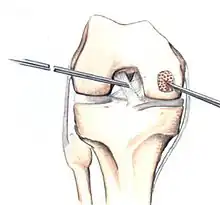

Arthroscopic image of OATS surgery on the medial femoral condyle of the knee

The choice of surgical versus non-surgical treatments for osteochondritis dissecans is controversial.[51] Consequently, the type and extent of surgery necessary varies based on patient age, severity of the lesion, and personal bias of the treating surgeon—entailing an exhaustive list of suggested treatments. A variety of surgical options exist for the treatment of persistently symptomatic, intact, partially detached, and completely detached OCD lesions. Post-surgery reparative cartilage is inferior to healthy hyaline cartilage in glycosaminoglycan concentration, histological, and immunohistochemical appearance.[52] As a result, surgery is often avoided if non-operative treatment is viable.